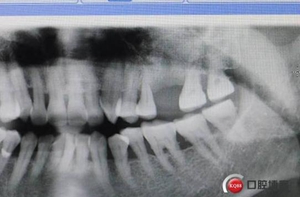

改良式外提升工具盒-外提 科貿(mào)嘉友收錄

大家好,我是梁老師的助理小依。由于梁老師每天手術(shù)檔期安排較滿,加上經(jīng)常出差講課,沒(méi)有時(shí)間整理病例 。為了方便大家更及時(shí)的了解梁老師最新手術(shù)動(dòng)態(tài),以后將由我為大家整理并推送梁老師最新經(jīng)典案例。案例文字旁白少,但圖片會(huì)盡量完整展示手術(shù)全過(guò)程,供大家學(xué)習(xí)參考。有任何問(wèn)題,可以留言,梁老師會(huì)親自為大家解答。感謝大家對(duì)梁老師的支持和關(guān)注!